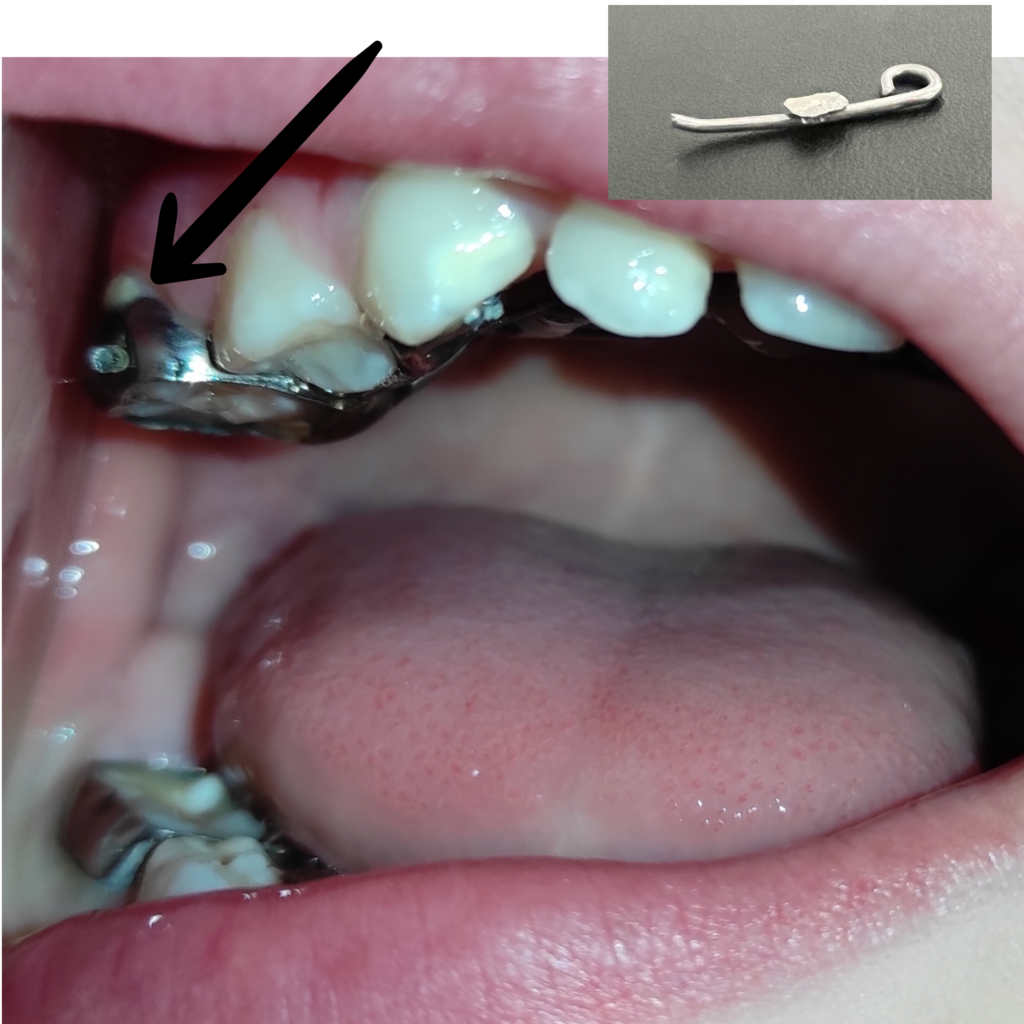

Aparell caigut completament

Aparell desenganxat

Aparell correcte

Aparell trencat